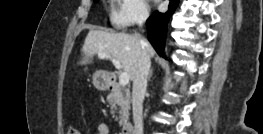

Мультиспиральная компьютерная томография с внутривенным болюсным контрастированием является наиболее точным и информативным методом диагностики патологии воротной вены. КТ основана на применении ионизирующего излучения и способности органов и тканей в разной степени поглощать рентгеновские лучи.

Для улучшения визуализации сосудистого русла пациенту внутривенно вводится йодсодержащий контрастный препарат. Рентгеновские лучи активно поглощаются контрастным веществом, поэтому на снимках хорошо видна сосудистая система воротной вены.

На снимках и трехмерных изображениях хорошо контрастируется сосудистая система воротной вены, участки сужения, визуализируются тромбы в просвете вены, также сеть коллатеральных сосудов, варикозно расширенные вены.